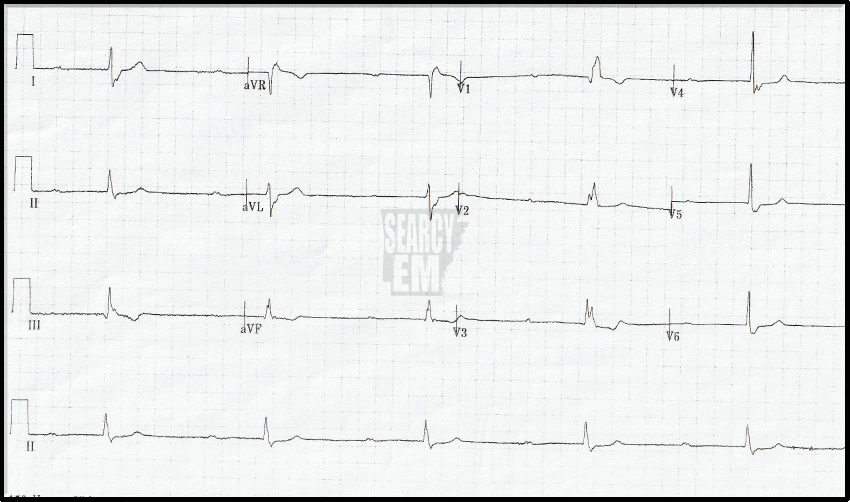

EKG 1: Interpretation